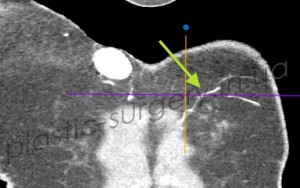

Рис. 11. Снимок компьютерной томографии с ангиографией № 1. Стрелкой обозначен второй перфорант внутренней грудной артерии слева. Контрлатерально визуализируется новообразование, получающее питание от первого перфоранта внутренней грудной артерии справа.

При проведении исследования был визуализирован и измерен второй перфорант внутренней грудной артерии справа, определено точное место выхода и его направление. Полученные данные позволили определить топографию не только перфоранта, но и его ветвей в покровных тканях (рис. 11, рис. 12), что было использовано при планировании дизайна лоскута.

Рис. 12. Снимок компьютерной томографии с ангиографией № 2. Стрелкой обозначен второй перфорант внутренней грудной артерии слева, визуализируются ветви перфоранта в покровных тканях.